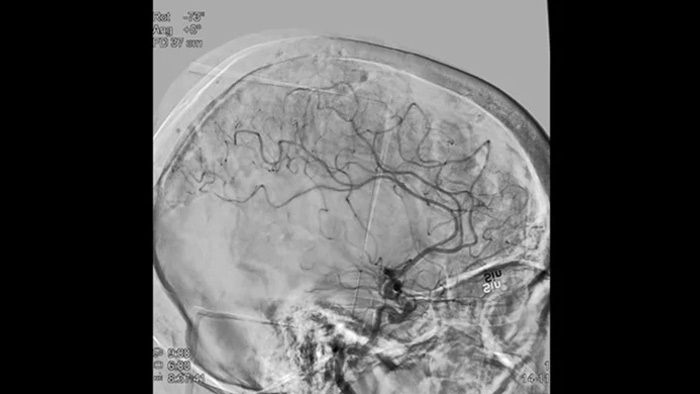

Imágenes nítidas con ASD 2D con tecnología ClarityIQ

ASD 2D con tecnología ClarityIQ

ClarityIQ aplica la compensación automática del movimiento durante la ASD en tiempo real para mantener imágenes nítidas de los vasos. Esto permite tomar decisiones con confianza durante los procedimientos para atender accidentes cerebrovasculares.

Visualización de la ASD

Las visualizaciones de la ASD de alta calidad le permiten evaluar si ha recuperado el coágulo completo y si los trozos de coágulo se han dispersado distalmente en el cerebro. Puede comprobar el restablecimiento del flujo sanguíneo en la penumbra y comprobar si hay hemorragias periprocedimiento.